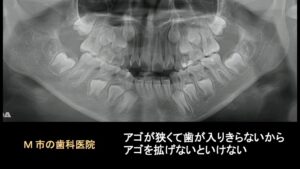

この患者さんは、8歳の時にM市の小児歯科医院でこのパノラマ写真を見せられて、顎が狭いので歯が入りきらない、顎を拡げなければいけない、早くしないと間に合わない、といわれ、治療を開始したそうです。

8歳時の模型では、将来的に叢生は予想されますが、模型を見る限り特に拡大する必要性はありません。